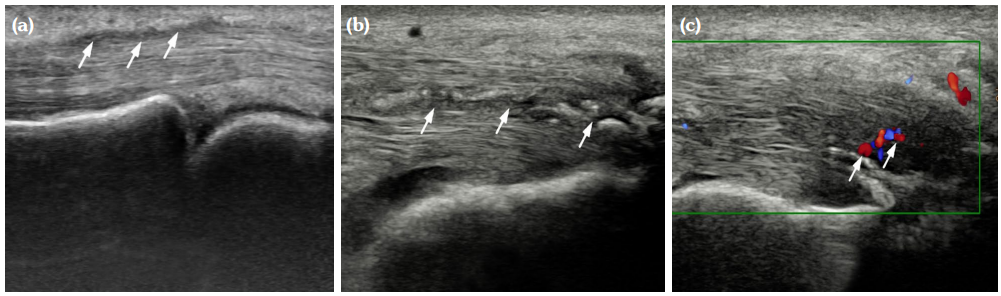

The degree of BE and synovial hyperplasia in SNRA or SPRA is more serious, and the blood flow signal is more abundant. However, the degree of synovial hyperplasia in osteoarthritis was mild, and no obvious blood flow signal was detected (Figures 1, 2, 3 and 4). Magnetic resonance imaging (MRI) studies of SPRA also showed serious BE (Figure 5).

Among SNRA, SPRA and non-RA, there was no significant difference in the grades of SH, PD, BE, nor the number of cases of tendinitis and tenosynovitis between the SNRA group and the SPRA group (p>0.05) (Table 3). There were, however, statistically significant differences in the number of cases of SH1, SH3, PD and BE grades between the SNRA and non-RA groups (p<0.001). There was no significant difference in the number of cases of SH2, PD2, tendinitis or tenosynovitis between the SNRA and non-RA groups (p>0.05) (Table 4).

We performed ultrasound scores on 30 hand joints of seronegative RA and non-RA patients, and the resulting SH, PD, and BE scores were selected from the most severely affected single joint (i.e., the one with the highest SH, PD, and BE scores). Next, we sequentially tested the sensitivity, specificity, positive predictive value (PPV), and negative predictive value (NPV) of each grade of SH, PD, and BE for the diagnosis of RA (Table 5). Accordingly, when the serological test was negative, PD Grade ≥2 or BE Grade ≥2 showed a higher sensitivity and specificity for diagnosing RA. When these two grading systems were combined and when either PD Grade ≥2 or BE Grade ≥2 was met, the optimal balance of high sensitivity (93.12%) and high specificity (91.30%) for diagnosing RA could be achieved.